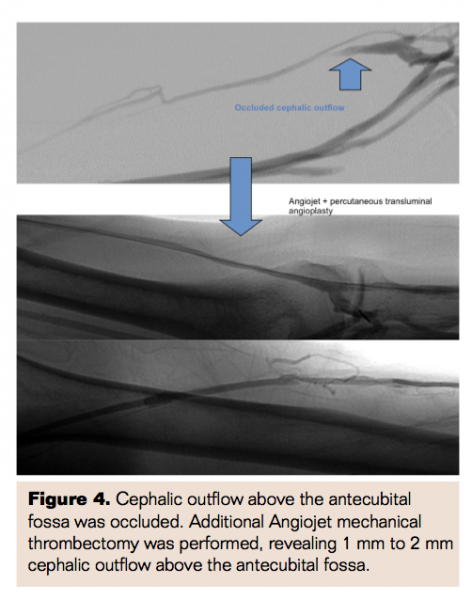

A micropunture needle was used to cannulate the proximal vein in an antegrade direction. A 6 Fr short sheath was then placed. An initial fistulogram showed the proximal AVF and anastomosis to be patent without stenosis. The middle cephalic vein appeared completely occluded, whereas the distal cephalic vein above antecubital fossa reconstituted but was 1 mm to 2 mm in size (Figure 1). A combination of Glidewire (Terumo) and Berenstein catheters was used to traverse the occluded segment. Five thousand units of heparin were administered and activated clotting time was maintained >200. Angiojet (Bayer HealthCare) mechanical thrombectomy was performed with 4 passes across the occluded segment (Figure 2). Balloon angioplasty was then performed to 6 mm at the previously thrombosed stenotic vein segment (Figure 3). In addition, the cephalic outflow above the antecubital fossa was noted to still be occluded. Additional Angiojet mechanical thrombectomy was performed, revealing a diminutively sized 1 mm to 2 mm cephalic outflow above the antecubital fossa (Figure 4). Additional angioplasty was performed on the small outflow vein to a final size of 6 mm. The central venogram demonstrated no residual stenosis (Figure 5).